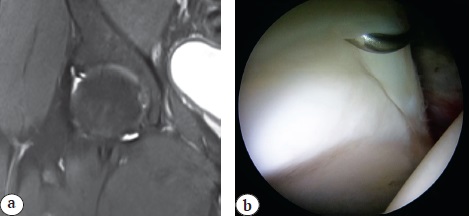

Вариантом комбинированной вне- и внутрисуставной патологии переднего отдела ТБС, сопутствующей ФАИ и выявленной по МРТ, является импинджмент-синдром m. psoas, сочетанный с внутрисуставным повреждением суставной губы и возможным наличием илиопектинальной бурсы или отека переднего края вертлужной впадины [84] (рис. 8, 9). Также стоит обратить внимание на строение сухожилия m. psoas, имеющее в 17% случаев две и более части, сохранение которых при тенотомии может повлечь рецидив импинджмента [85].

Рис. 8. Разрыв губы вертлужной впадины (белая стрелка) с формированием кисты (черная стрелка)

Fig. 8. Acetabulum labrum rupture (white arrow) with cyst formation (black arrow)

Рис. 9. Отек переднего края вертлужной впадины (черная стрелка) в проекции сухожилия m. psoas (белая стрелка)

Fig. 9. Edema of acetabulum anterior edge (black arrow) in the projection of tendon m. psoas (white arrow)